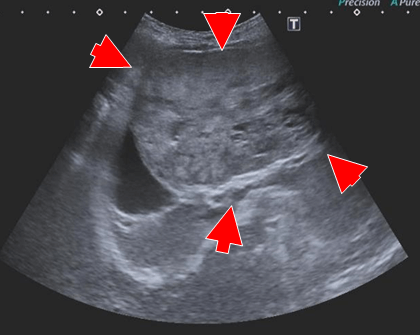

腹部超音波検査

― 右上腹部に40mm大の腫瘤陰影

― 腹腔内に液体貯留

― 穿刺吸引→血様の液体

CT(第2病日)

肝動脈尾状葉枝が栄養血管門脈血の流入は確認されず

尾状葉由来5cm大

動脈相

門脈相

CT MIP

【診断・治療方針】

腹腔内腫瘤の破裂による非外傷性出血

― 腹腔内腫瘤は肝尾状葉由来 (Φ5cm)

腫瘤は動脈相で早期膿染

― 肝動脈尾状葉枝が栄養血管